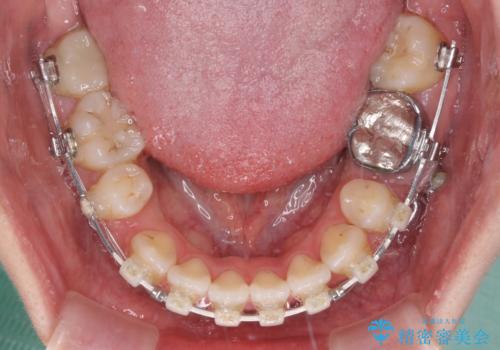

- ハーフリンガル

- 2年8ヶ月

開咬の改善には舌突出癖を改善するためのトレーニングが必要ですが、しっかりと行っていただき、想定よりも早い期間で治療を終えることができました。